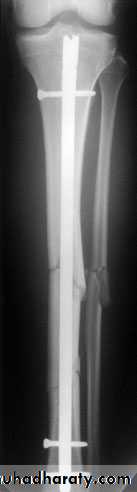

1-Closed intramedullary nailing This is the method of choice for internal fixation. The fracture is reduced under x-ray control and image intensification. For diaphyseal fractures, union can be expected in over 95 per cent of cases. However, the method is less suitable for fractures near the bone ends.

2-Plate fixation is best for metaphyseal fractures that are unsuitable for nailing. It is also sometimes usedfor unstable tibial shaft fractures in children.

3-External fixation This is an alternative to closed nailing; it avoids exposure of the fracture site and allows further adjustments to be made if this should be needed.

Operative treatment